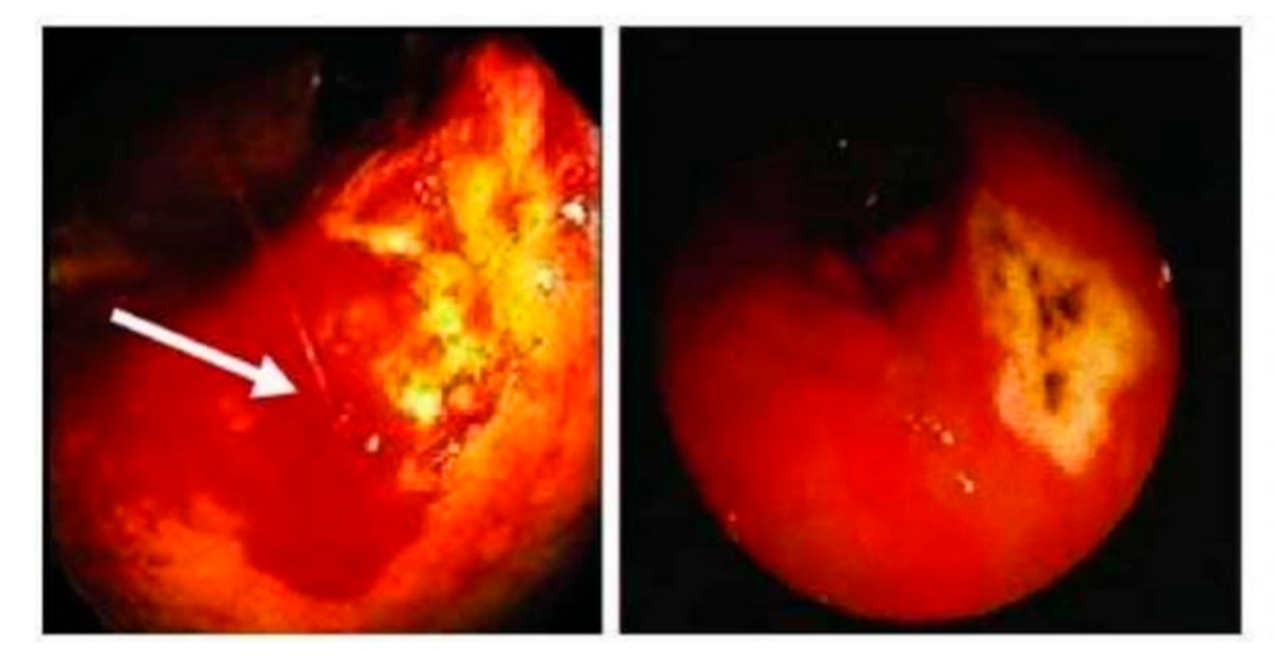

2.2. Endoscopic Examination

3.2. Endoscopic Findings